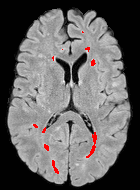

Patch size is another important parameter of the network. In computer vision applications such as object detection, usually a whole 2D image is used as a feature. However, full 3D medical images can not typically be used because of memory limitations. Fig. 4 shows examples of lesion memberships obtained with different sized 2D patches. As the patch sizes increases, the false positives that are mostly observed in the cortex tend to decrease. Fig. 5 shows a plot of Dice and LFPR with various patch sizes, ordered from left to right according to their increasing size. Note that smaller patches ( to ) produced significantly lower Dice and higher LFPR compared to other patches (), as seen from the memberships in Fig. 4. Also some of the highest Dice and lowest LFPR were observed for patches with large in-plane size, i.e., , , and . It was observed in Fig. 5 that there is no significant difference between Dice coefficients for , , or , but LFPR of both and are significantly lower than that of (). We chose as the optimal patch size. Other choices of smaller and patches (not shown) yielded worse results. Note that although training was performed with different patch sizes, the memberships were generated slice by slice, as the trained model consisted only of convolutions and did not need any information about patch sizes.

For this dataset, the training was performed separately with two sets of masks from the two raters of ISBI-21 data. Then two memberships were generated for each of the images. For each image, the two memberships were averaged and thresholded to form the final segmentation. Fig. 6 shows MR images and segmentations of subjects from the MS-100 dataset, where the subjects have high (cc), moderate (cc), and low (cc) lesion loads. For the subject with high lesion loads (#1), all methods performed comparably, although OASIS and LST underestimated some small and subtle lesions (yellow arrow). For the subject with moderate lesion load (#2), OASIS and S3DL underestimated some lesions (orange arrow) and LesionTOADS overestimated some (green arrow). When the lesion load is small and the FLAIR image has some artifacts (subject #3), LesionTOADS, S3DL, and OASIS produce a false positive (yellow arrow) in the cortex. LST shows underestimation, but FLEXCONN does not produce the false positive. The reason is partly because of the use of large patches, which can successfully distinguish between bright voxels in cortex and peri-ventricular regions.